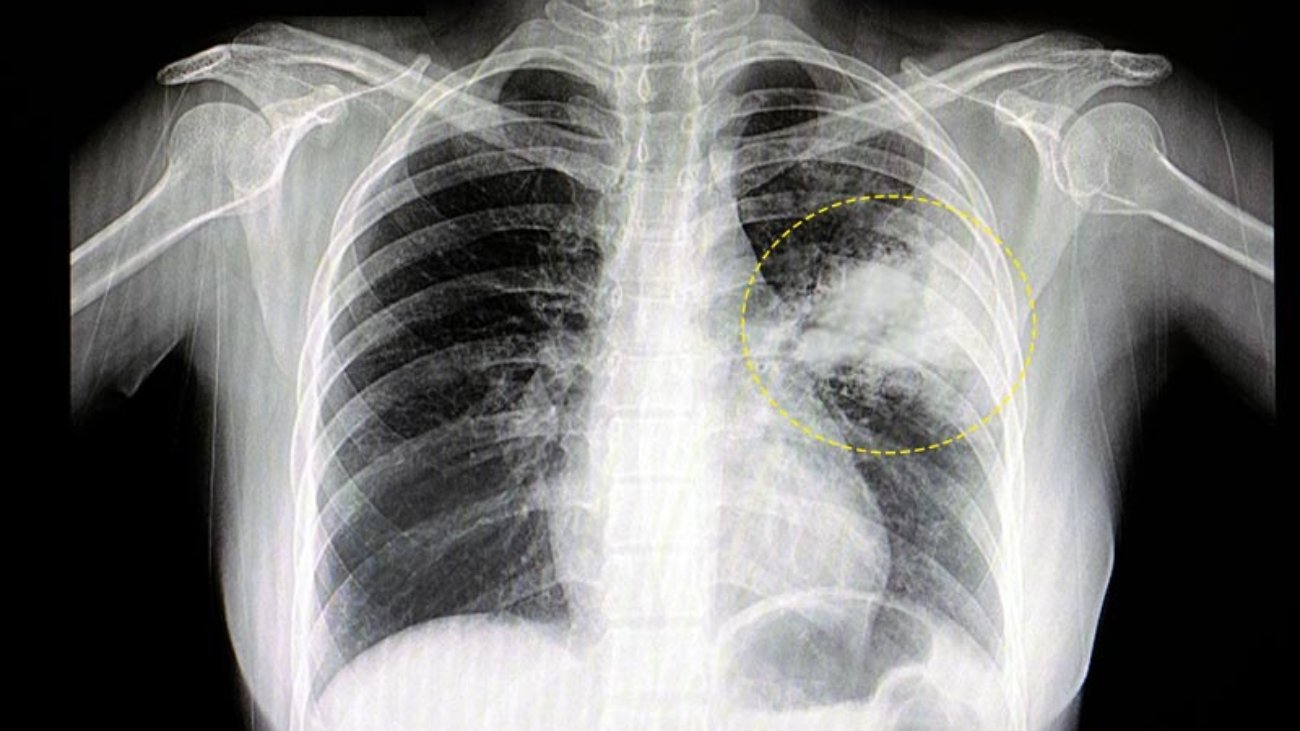

Todo sobre neumonia, trabajo especial.

Muchos asocian la neumonía con los ancianos, pero en realidad es la principal causa de muerte infecciosa entre niños en todo el mundo. Cada año, la neumonía se cobra la vida de más de 725.000 niños menores de cinco años, incluidos alrededor de 190.000 re ...